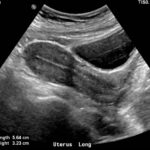

- Ecografía Prostática

- Ecografía Transvaginal